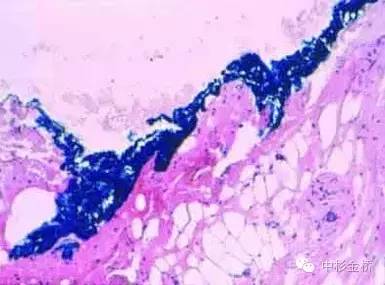

3、應(yīng)用于脂肪組織時(shí),可用噴壺噴灑少量丙酮對組織表面進(jìn)行脫脂處理,擦拭干后再使用色標(biāo)劑進(jìn)行染色。尤其適用于乳腺和皮下組織。